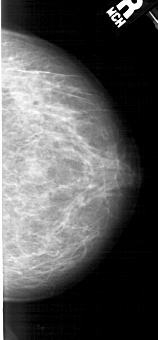

A_1982_1.LEFT_CC

LEFT_CC LINES 4921 PIXELS_PER_LINE 2461 BITS_PER_PIXEL 12 RESOLUTION 43.5 OVERLAY